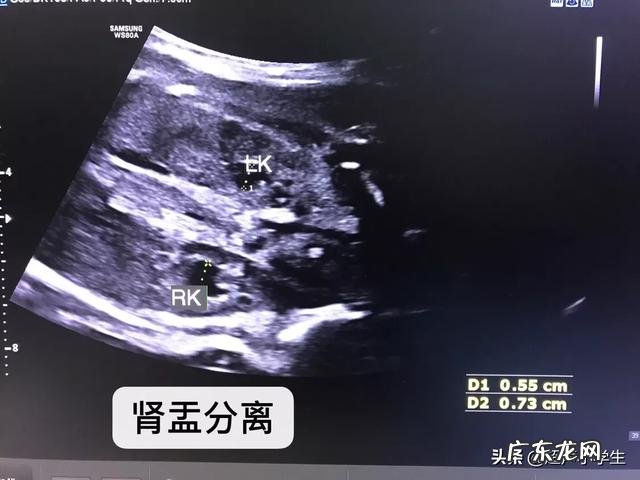

由于男女生殖系统的差异,发现肾盂分离的宝宝是男宝宝的可能性要大一些 。特别强调只是可能性,也有女宝宝有肾盂分离的 。只是说是男宝宝的概率大一点 。